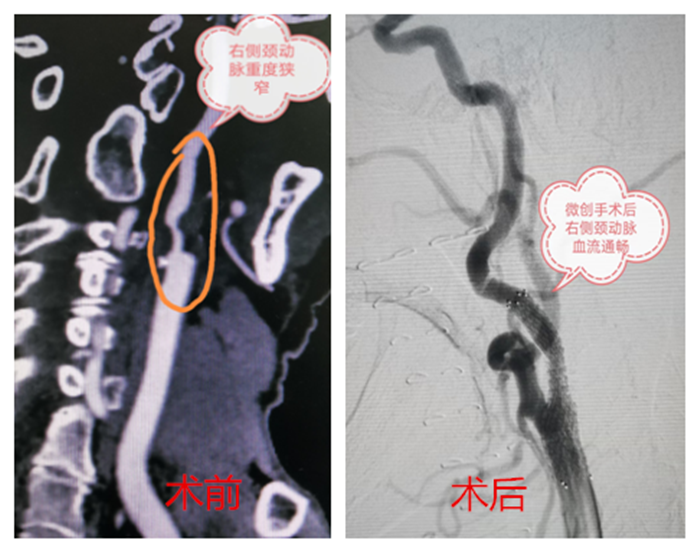

血管外科接診醫(yī)生程國兵仔細(xì)問詢并完善相關(guān)檢查,經(jīng)頸動脈CT血管成像提示:右頸內(nèi)動脈起始段少量混合斑,管腔中重度狹窄。頭顱磁共振提示:右側(cè)急性腦梗。

在科主任陸煒的帶領(lǐng)下,血管外科診療團(tuán)隊(duì)為祝老先生行“超選擇性右頸動脈造影+支架植入球囊擴(kuò)張術(shù)”。在非插管全麻下,穿刺右股動脈,置入動脈鞘,導(dǎo)絲通過動脈鞘進(jìn)入右頸總動脈,在右頸動脈狹窄段遠(yuǎn)3厘米處放置保護(hù)傘導(dǎo)絲,沿著導(dǎo)絲放置球囊,用球囊壓力泵擴(kuò)張狹窄段,退出球囊后,在狹窄段成功置入支架。短短一個(gè)小時(shí),手術(shù)順利完成。